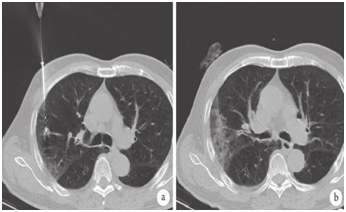

近期,馬鞍山市人民醫(yī)院胸心外科在麻醉科、CT室的協(xié)助下,連續(xù)成功為3例肺部小結節(jié)患者作了微創(chuàng)微波消融術。3例病變均在1cm左右(兩例實性結節(jié),1例磨玻璃結節(jié))。術前對小結節(jié)作充分的討論分析,術中精確定位、穿刺活檢,并進行精準消融治療,術后未發(fā)生任何并發(fā)癥,次日出院。

患者微波消融術中和術后即刻 CT 檢查表現(xiàn)